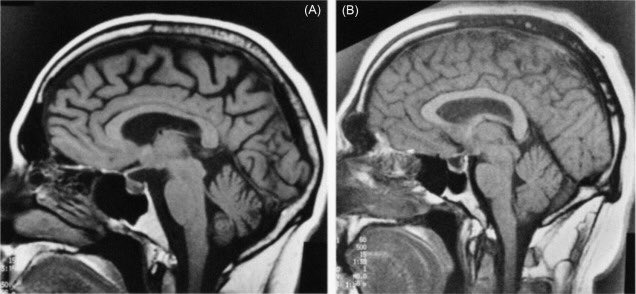

عادةً مايتضمن التشخيص اختباراً بدنياً يتبعه اختباراتٍ معينةٍ،ويظهر ضمور الدماغ في عمليات مسح تصوير الدماغ منها:

*الرنين المغناطيسي(MRI)الذي يخلق صوراً دماغيةً عالية الدقة للتشخيص